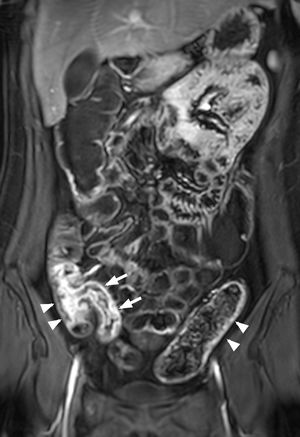

El CGd está indicado en la enterografía por RM para identificar la presencia y severidad de la actividad inflamatoria y la detección de complicaciones. Generalmente, se obtienen imágenes T1-TEG con supresión grasa en el plano coronal poscontraste en la fase portal (60 s) (fig. 7), aunque algunos autores adquieren cuatro fases: sin contraste, arterial (20-25 s), portal (60 s) y equilibrio (120 s). Tras el plano coronal, se realizan secuencias T1-TEG con supresión grasa en los planos transversal y sagital45,46.

Mujer de 20 años. La RM intestinal con CGd demuestra un realce de la pared de un segmento de 7cm de íleon terminal (flechas) y de 8cm de ciego y colon ascendente (punta de flecha) y realce en la pared del colon descendente (puntas de flecha), por enfermedad de Crohn, con actividad inflamatoria.

CGd: contraste de gadolinio; RM: resonancia magnética.